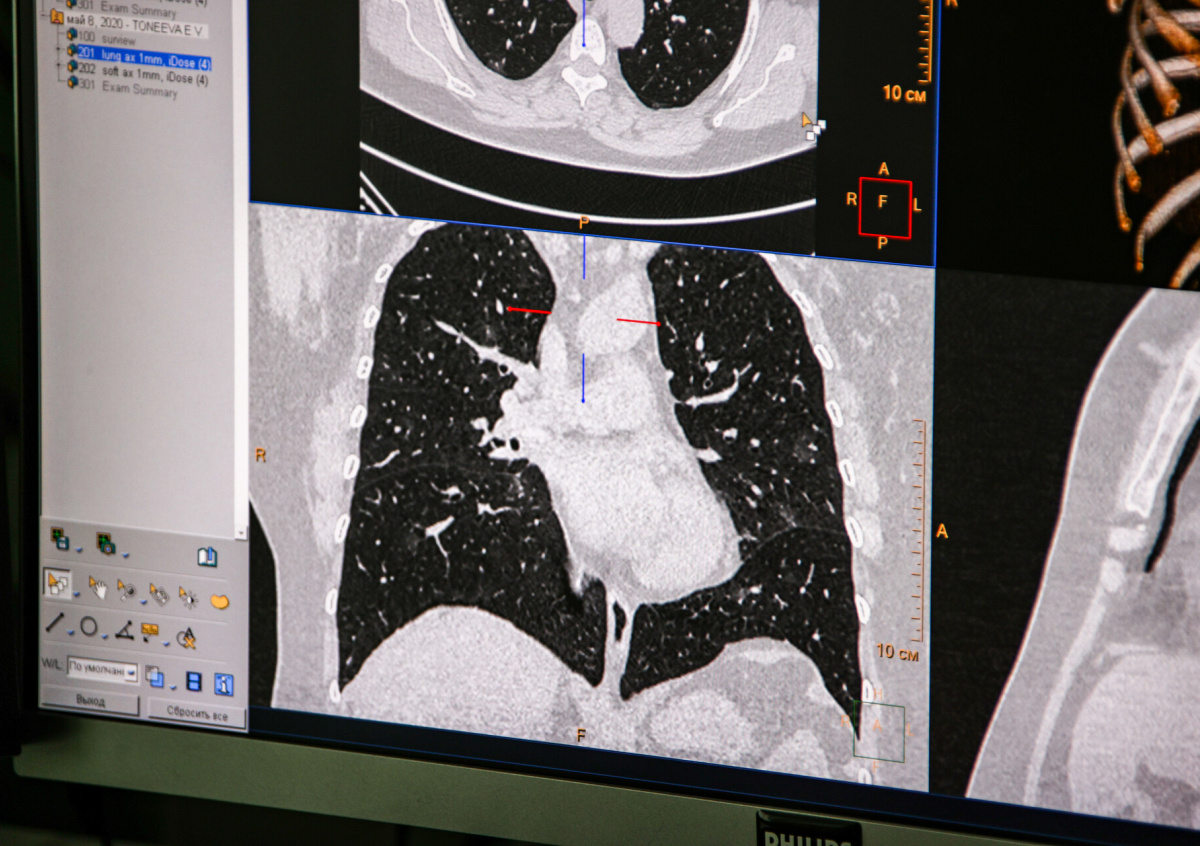

Мишустин заявил, что ситуация с коронавирусом в России остаётся непростой

Ситуация с коронавирусом в России остаётся непростой, заявил премьер-министр Михаил Мишустин в ходе совещания с вице-премьерами.

В России число заболевших за сутки составило 15 982. 5328 ранее заразившихся вылечились, 179 человек скончались.